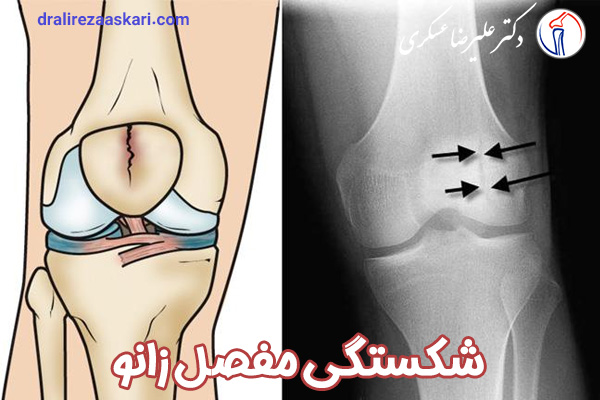

عکس سی تی اسکن شکستگی مفصل زانو

معاینه : درمان شکستگی کشکک زانو به نوع استخوانتان بستگی دارد. پزشکتان ابتدا زانویتان را معاینه کرده و علائم خونریزی داخل مفصلی را بررسی می کند. برای درمان خونریزی داخل مفصلی شاید نیاز باشد ابتدا مقداری از خون را تخلیه کند. سپس برای تشخیص نوع شکستگی از آن عکس برداری می کند. اگر شکستگی مفصل زانو پایدار باشد احتمالاً استخوانتان بدون عمل درمان شود.